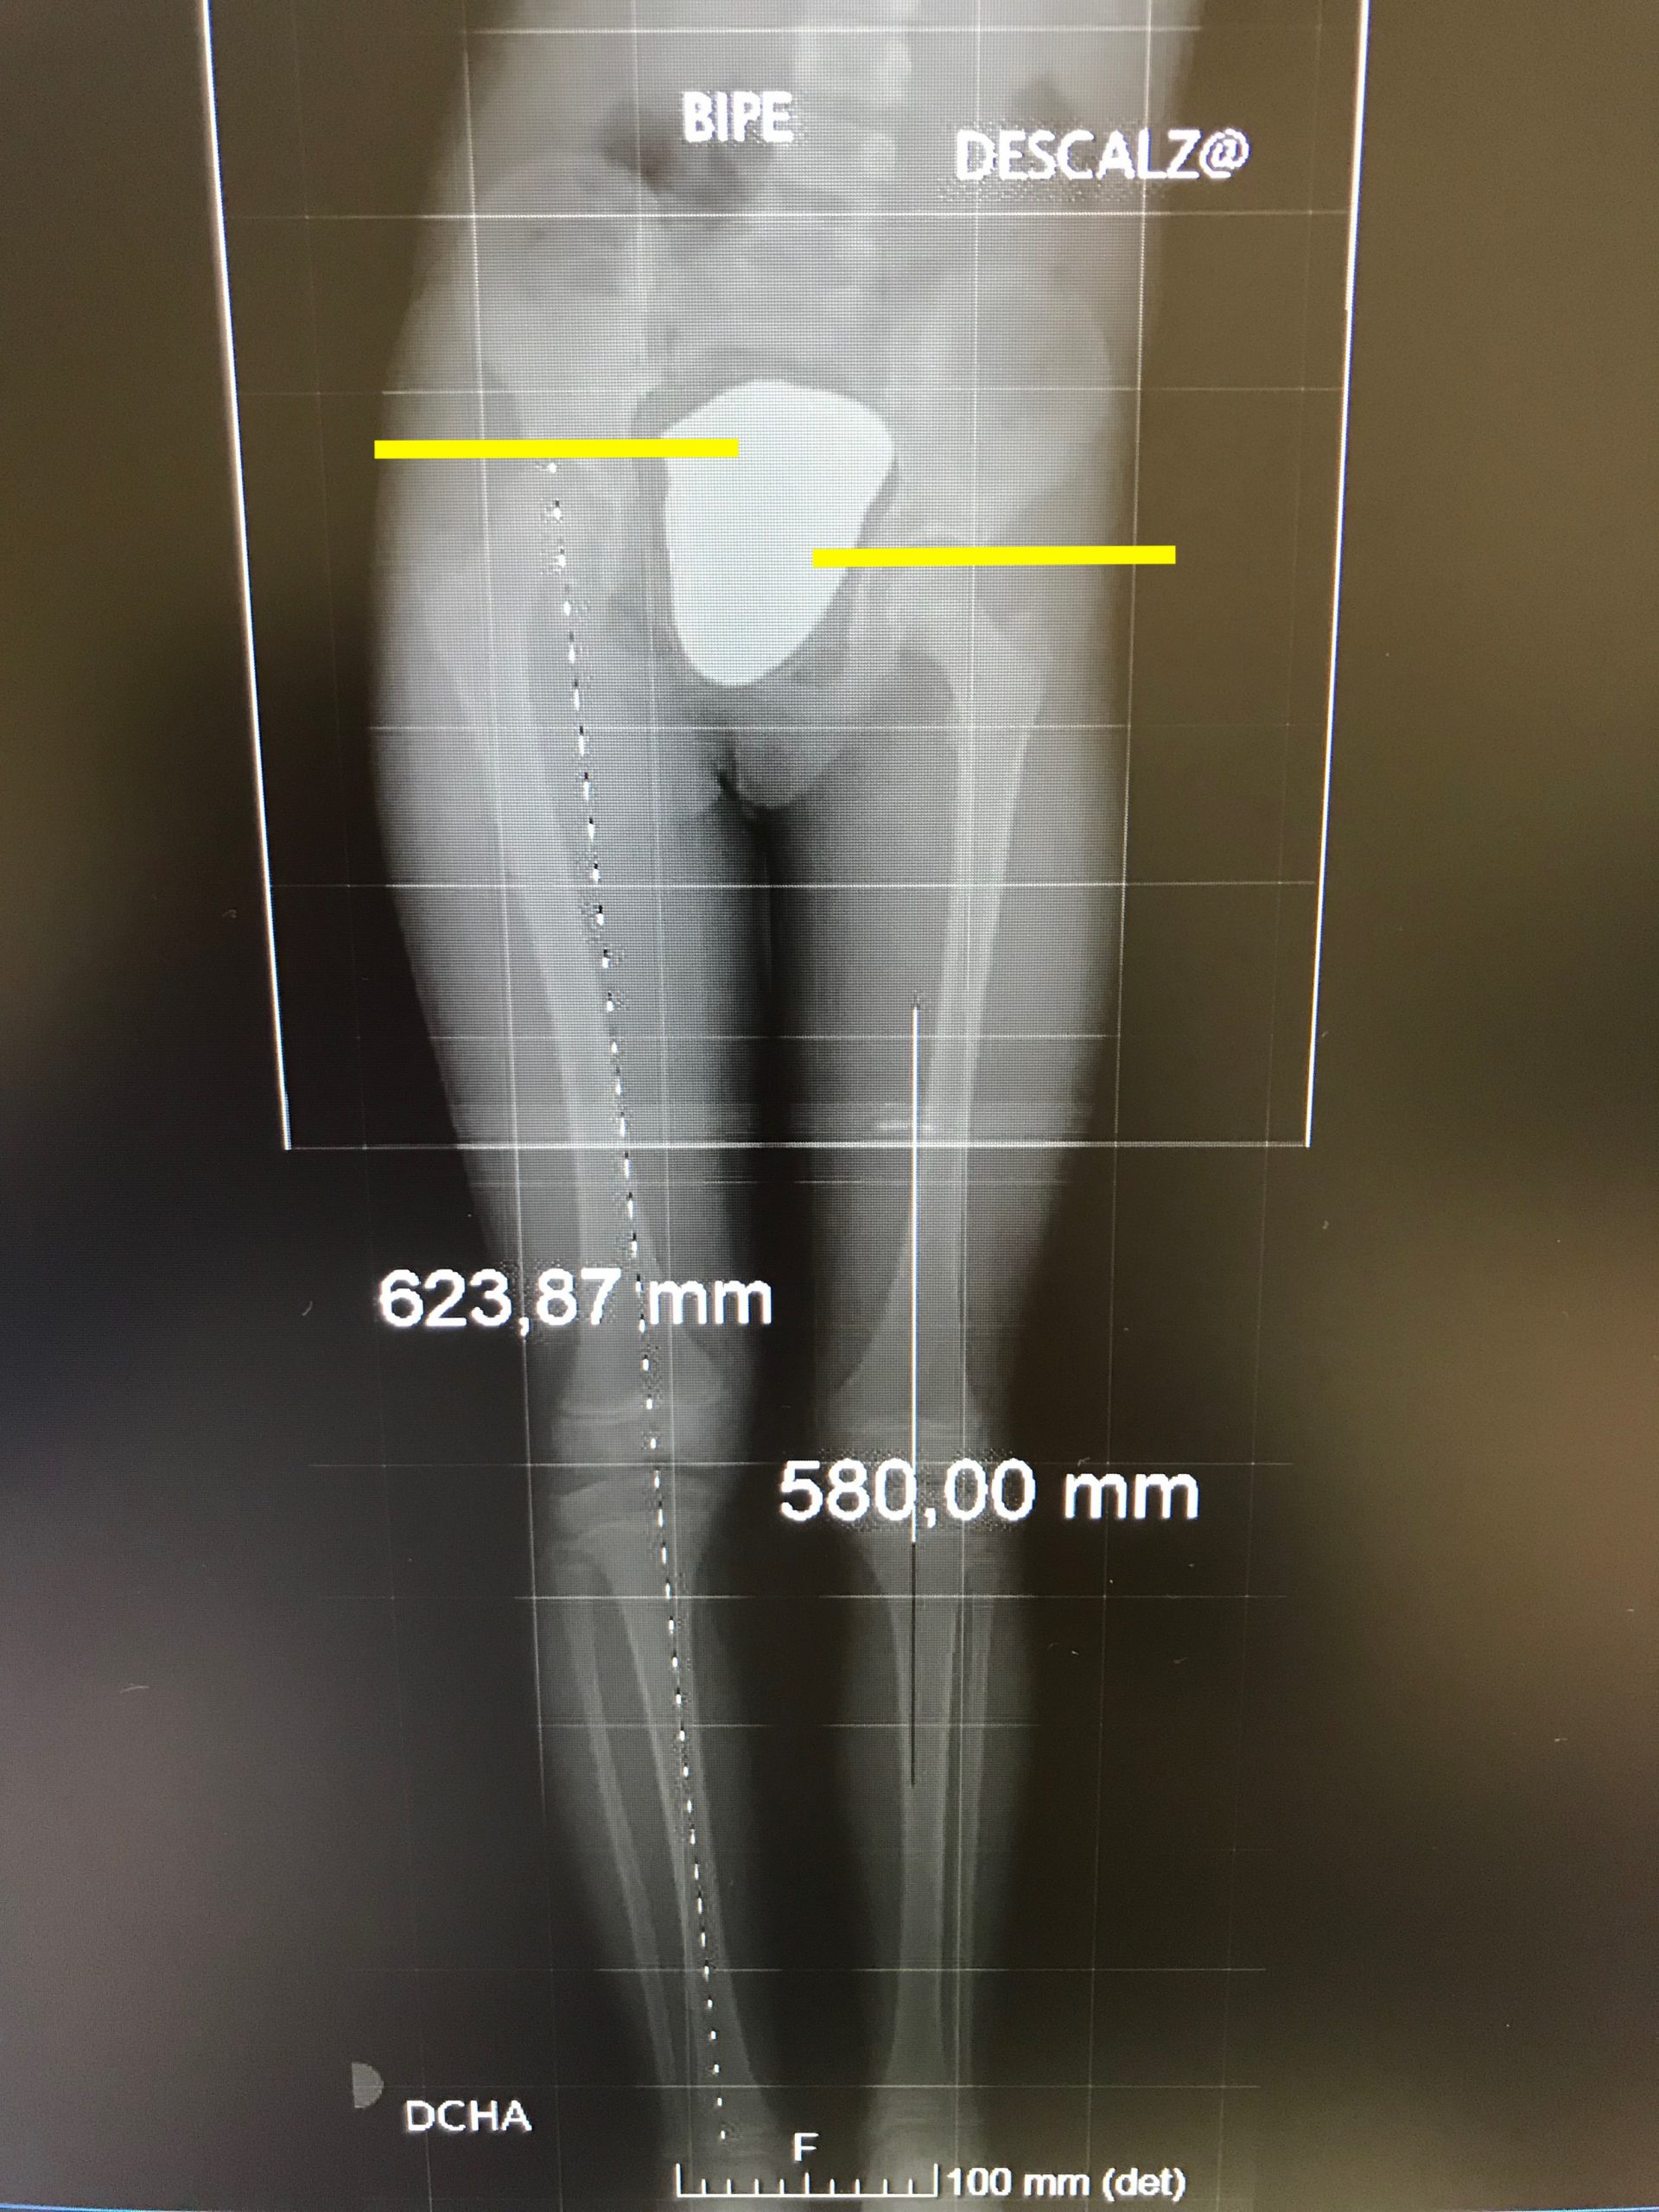

dismetría